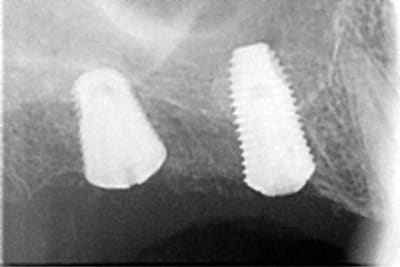

comme ce petit cas

la 2ème radio est prise 18 mois après la 1ère

PS pour Gulguch c'est bien un implant de 6 mm de diamètre en distal et pourtant pas la moindre perte osseuse...

si tu regarde bien la radio il y a une "esquille" (tarte ou /et ciment) entre les deux piliers et mauvais "joint" donc il ne faut peut être pas accuser l'implant dans ce cas là.

je voulais justement signifier l'inverse cad malgré des "soucis" de tartre et joint le niveau osseux est au dessus de l'implant